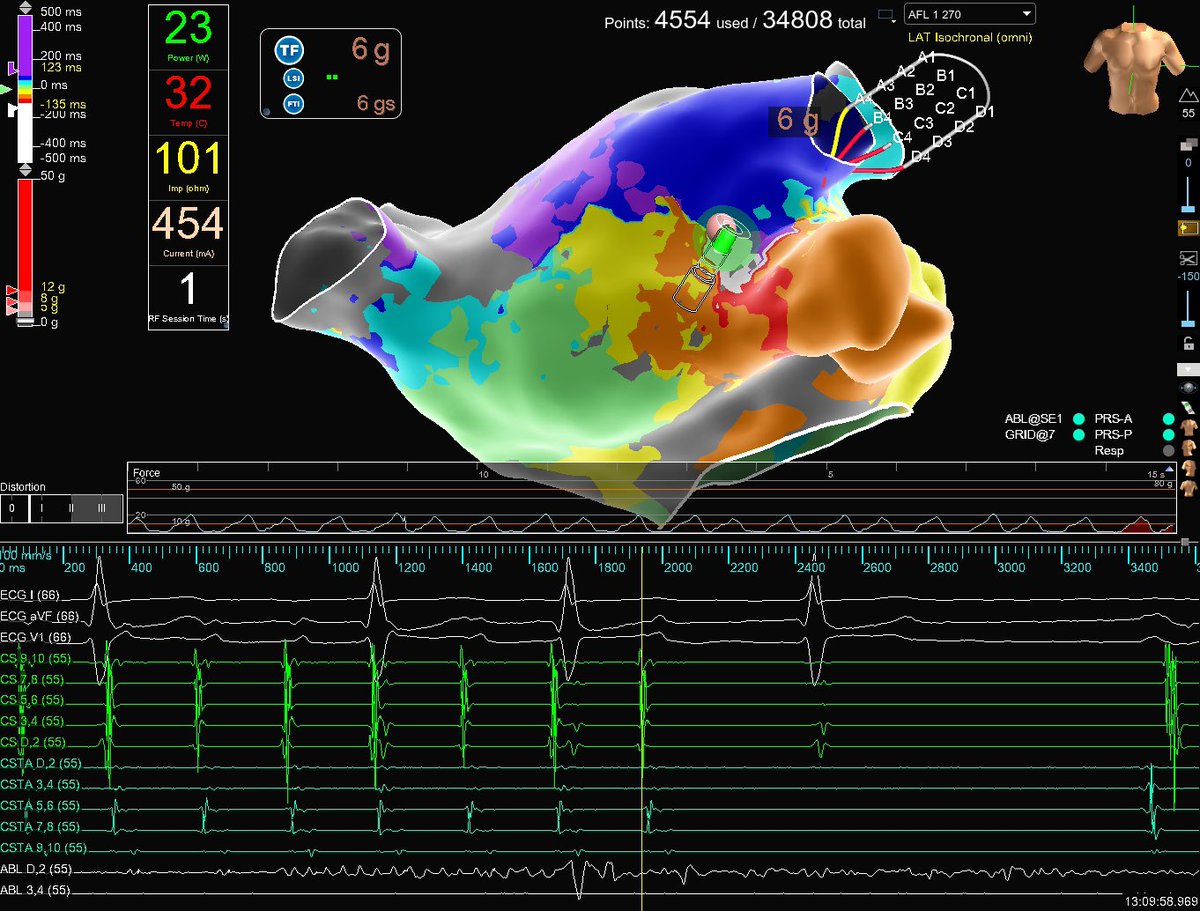

Incessant Parahisian AT w/earliest signals mapped to right anterior septum w/sharp HIS deflection present. Detailed mapping of NCC with #HDGrid on #EnsiteX allowed for safe ablation (w/o HIS signal present) and termination of AT in 3 seconds. Abbott Cardiovascular Map credit: Chelsea Paskman

Incessant Parahisian AT w/earliest signals mapped to right anterior septum w/sharp HIS deflection present. Detailed mapping of NCC with #HDGrid on #EnsiteX allowed for safe ablation (w/o HIS signal present) and termination of AT in 3 seconds. <a href="/AbbottCardio/">Abbott Cardiovascular</a> Map credit: <a href="/CPaskman/">Chelsea Paskman</a>